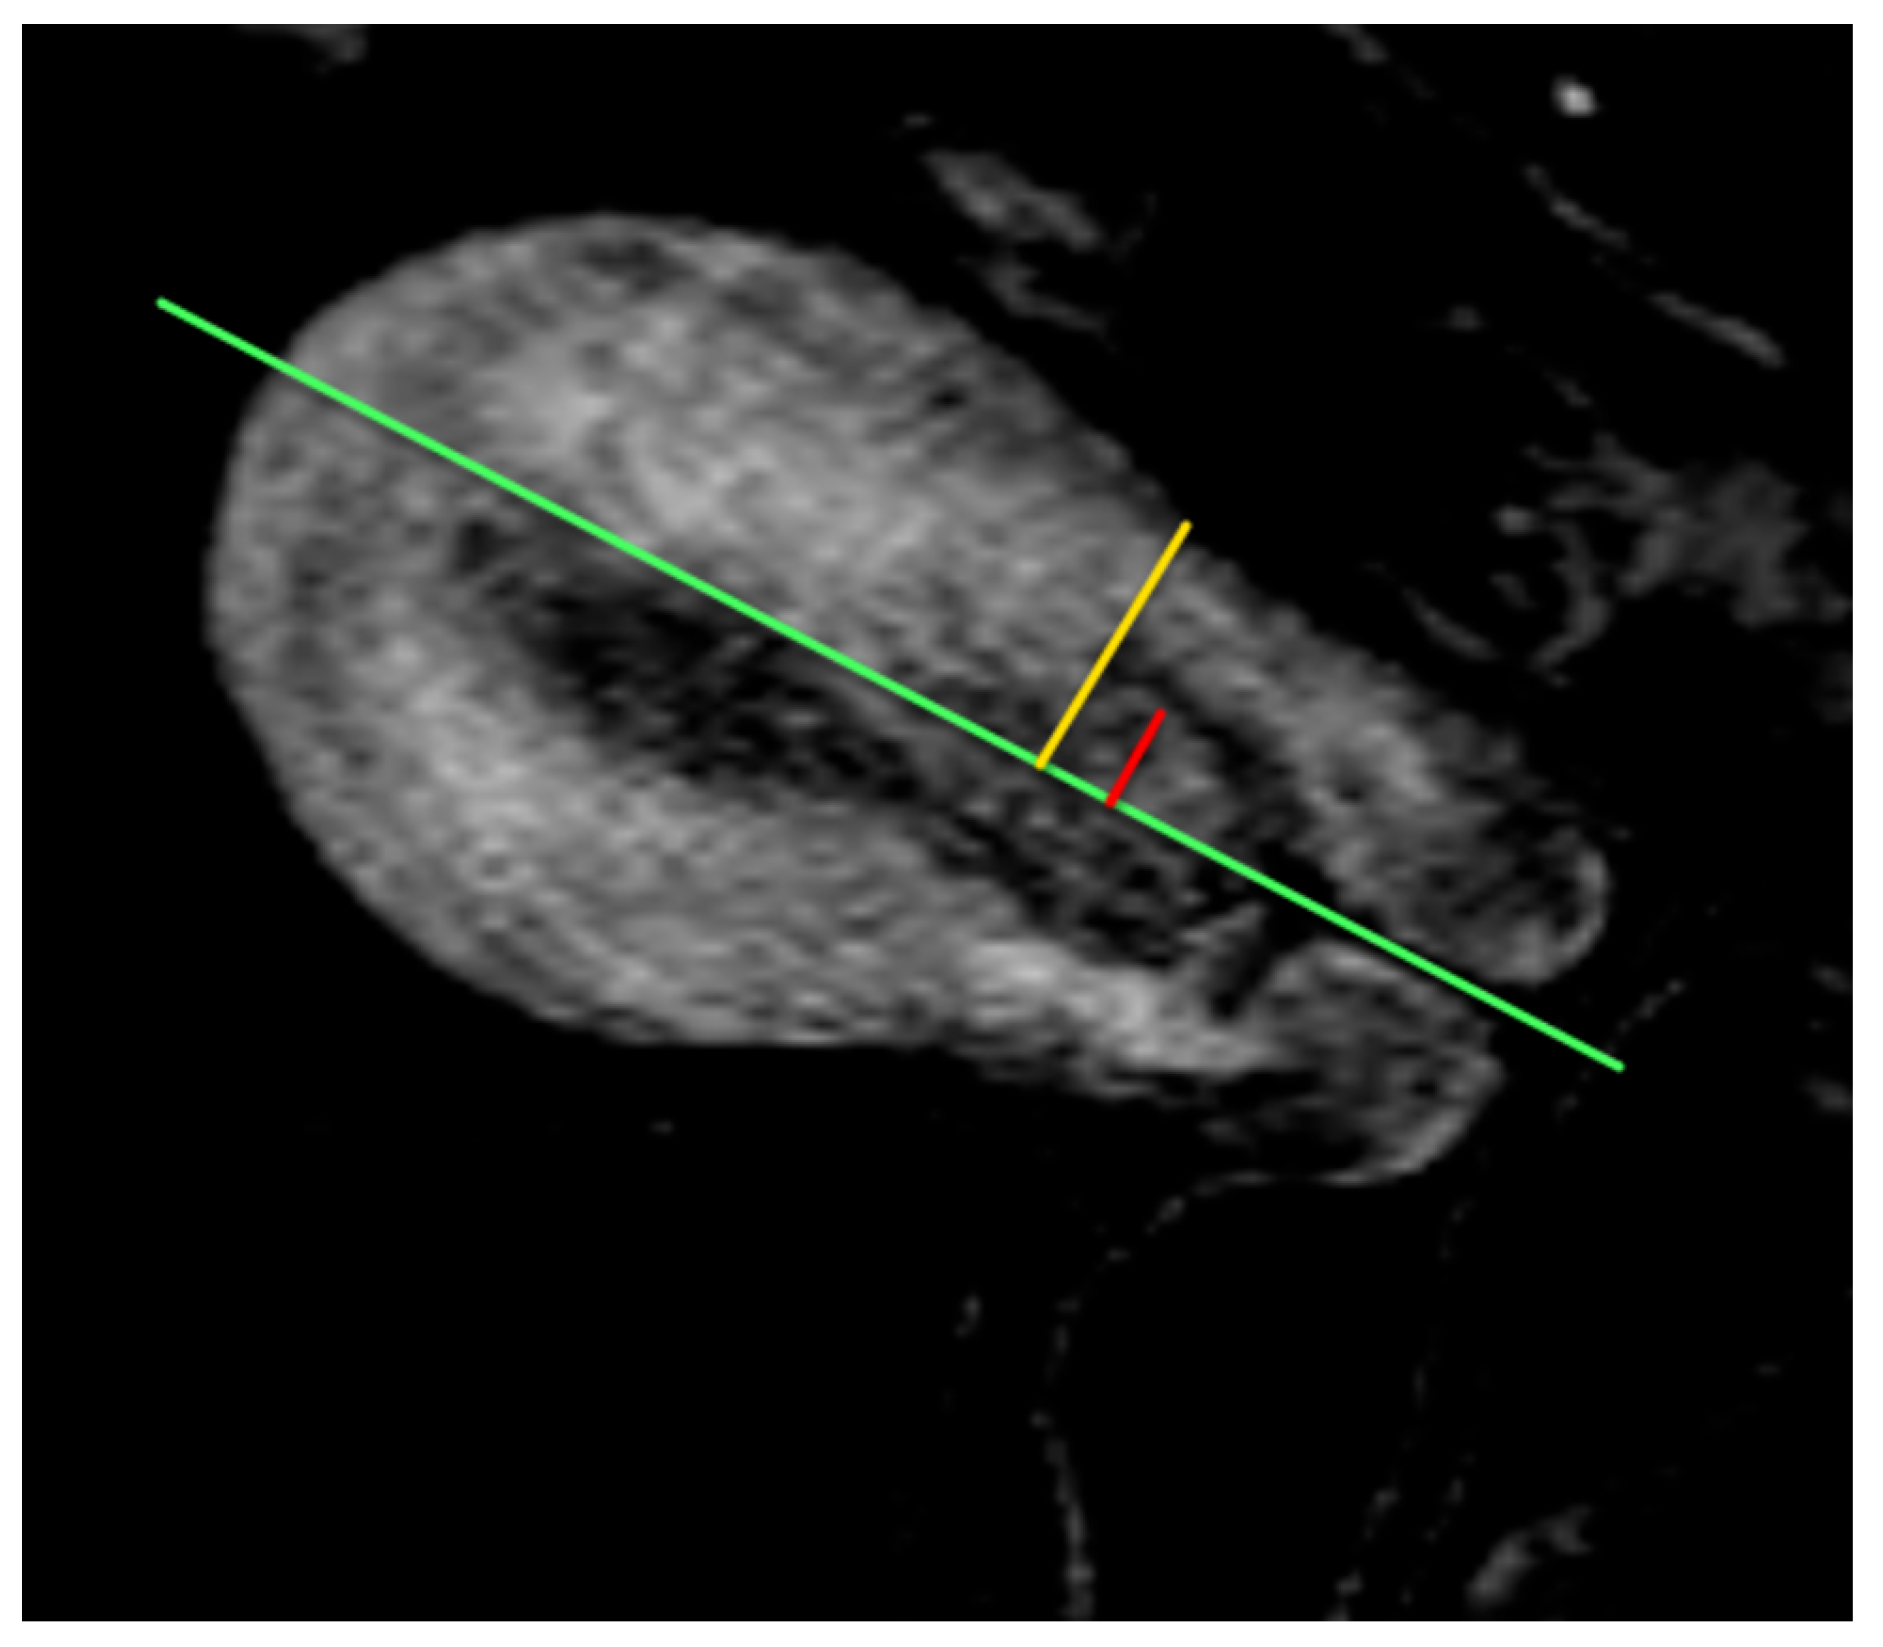

5.3. Magnetic Resonance Imaging (MRI)

- Maheshwari, E.; Nougaret, S.; Stein, E.B.; Rauch, G.M.; Hwang, K.-P.; Stafford, R.J.; Klopp, A.H.; Soliman, P.T.; Maturen, K.E.; Rockall, A.G.; et al. Update on MRI in Evaluation and Treatment of Endometrial Cancer. RadioGraphics 2022, 42, 2112–2130. [Google Scholar] [CrossRef] [PubMed]

- Rechichi, G.; Galimberti, S.; Signorelli, M.; Franzesi, C.T.; Perego, P.; Valsecchi, M.G.; Sironi, S. Endometrial Cancer: Correlation of Apparent Diffusion Coefficient With Tumor Grade, Depth of Myometrial Invasion, and Presence of Lymph Node Metastases. Am. J. Roentgenol. 2011, 197, 256–262. [Google Scholar] [CrossRef]

- Keles, D.K.; Evrimler, S.; Merd, N.; Erdemoglu, E. Endometrial cancer: The role of MRI quantitative assessment in preoperative staging and risk stratification. Acta Radiol. 2022, 63, 1126–1133. [Google Scholar] [CrossRef] [PubMed]

- Nougaret, S.; Reinhold, C.; Alsharif, S.S.; Addley, H.; Arceneau, J.; Molinari, N.; Guiu, B.; Sala, E. Endometrial Cancer: Combined MR Volumetry and Diffusion-weighted Imaging for Assessment of Myometrial and Lymphovascular Invasion and Tumor Grade. Radiology 2015, 276, 797–808. [Google Scholar] [CrossRef]